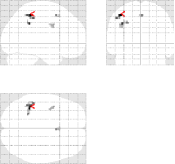

Fig. 12 reports similar group-level MIP results for and concerning the Lc-Rc contrast.

| mSENSE | UWR-SENSE | 4D-UWR-SENSE | |

|---|---|---|---|

|

|

|

|

|

|

|

It is shown that whatever the acceleration factor in use, our pipeline enables to detect a much more spatially extended activation area in the motor cortex. This visual inspection is quantitatively confirmed in Tab. 6 when comparing the detected clusters using our 4D-UWR-SENSE approach with those found by mSENSE, again irrespective of . Finally, the 4D-UWR-SENSE algorithm outperforms the UWR-SENSE one, which corroborates the benefits of the proposed spatio-temporal regularization scheme.